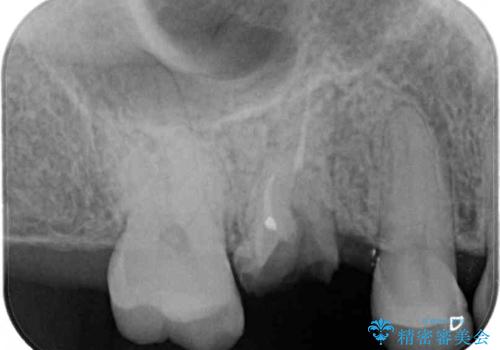

- 近医で奥歯の抜歯が必要であると指摘され、インプラント治療を希望して来院された患者様です。

診察の結果、大きな虫歯となっている歯は抜歯が望ましく、抜歯後にストローマンSLActiveを埋入することとしました。

さらに後方の歯は虫歯治療が途中であったため、ゴールドインレーにて修復治療行うこととしました。